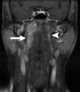

Enlarged lateral retropharyngeal lymph node